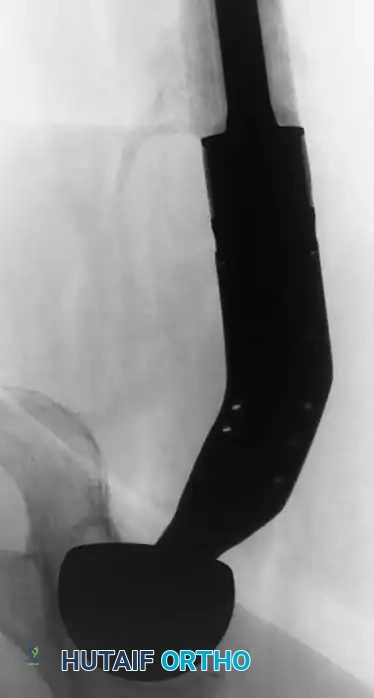

Fig. 22-19: (A) Anteroposterior view of the left hip of a 50-year-old woman with a history of breast cancer, disease-free for 2 years. A lytic lesion is seen in the femoral neck. Although the most likely diagnosis is metastatic carcinoma, a biopsy must be performed. This lesion proved to be a malignant fibrous histiocytoma (primary sarcoma). (B) Anteroposterior view after wide resection and endoprosthetic reconstruction. Prophylactic fixation of this presumed metastasis would have severely compromised her oncologic outcome.